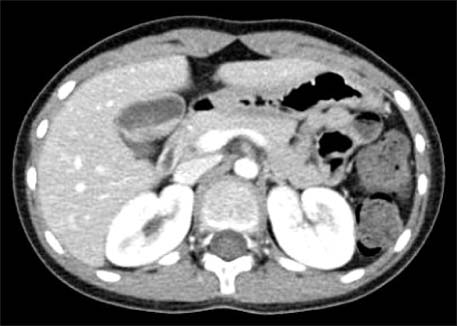

Fig. 2

Ultrasonography performed at the emergency room shows multiple gallbladder sandy stones with sludge (case 2).